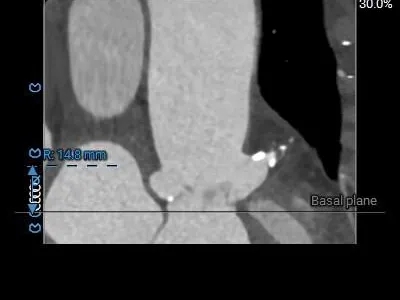

术前CT分析

主动脉根部测量

Annulus

23.8mm

LVOT

22.4mm

钙化积分

535

SOV

STJ

28.5mm

AAO

42.4mm

横列式Type0型二叶瓣,瓣环内径23.8mm

流出道收口型

瓣叶显著增厚、重度偏心钙化

升主扩张

瓣上结构测量

瓣上2mm

21.6mm

瓣上4mm

21.9 mm

瓣上6mm

21.7 mm

瓣上8mm

21.7mm

瓣上10mm

21.1mm

瓣下2mm

22.2mm

瓣上限制较重,可见明显左窦瓣叶偏心钙化,限制最重区域为瓣上4-8mm。